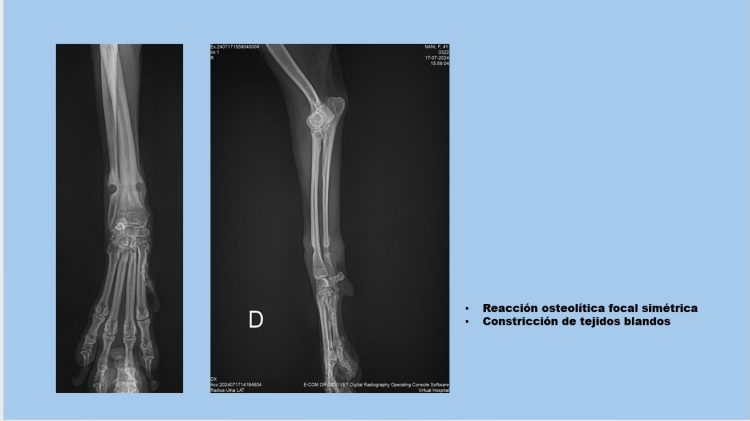

La médico De la Cruz, del Instituto de Ciencias Biomédicas (ICB) de la Universidad Autónoma de Ciudad Juárez (UACJ), ganó el primer lugar en la categoría de presentaciones clínicas con el trabajo “Síndrome de la banda elástica en perro: presentación de un caso clínico”.

De la Cruz explica que este síndrome es poco común de perros, sin embargo, puede generar consecuencias graves si no se detecta a tiempo; al investigar sobre estos casos, encontró registros de la India y de Estados Unidos. El síndrome de la banda elástica es cuando a un perro o gato se le encarna una liga en su pata o en su cola y esta llega hasta el hueso y la piel la recubrir, causando que los animales tengan una cojera sin poder saber la causa.